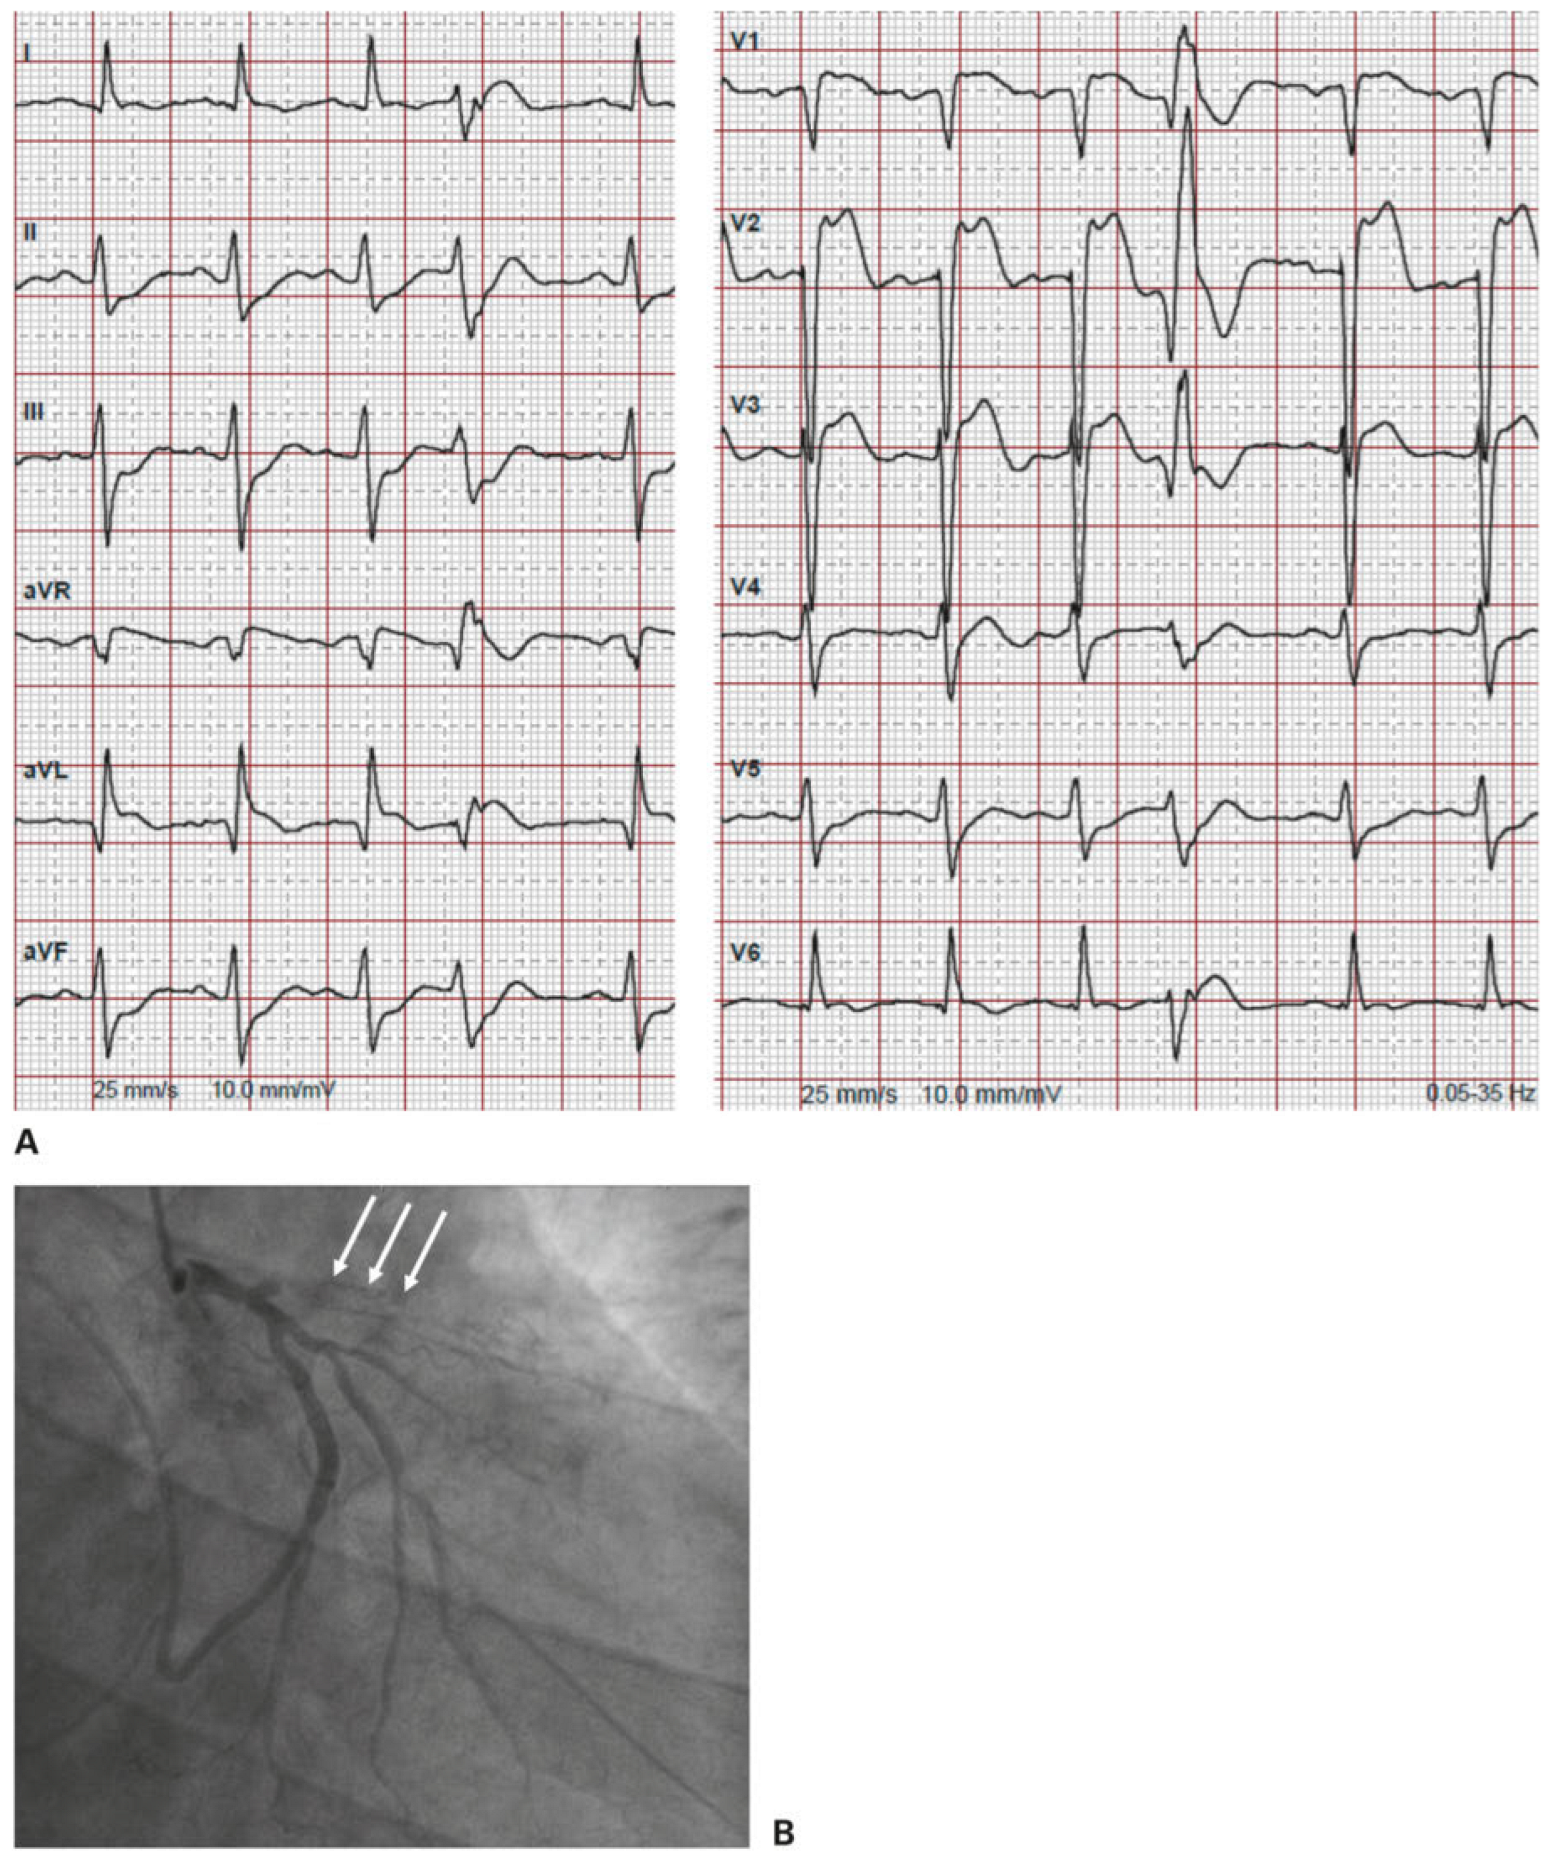

Regardless of the correct identification of ventricular tachycardia, from the emergency point of view, the question of whom you treat first depends on the patient’s stability. Patient 2 was unstable on arrival at the ED. He was immediately transferred to the shock room where the advanced cardiac life support (ACLS) algorithm for stable/unstable tachycardia was applied (Figure 4, adapted from [4]). As the patient had hypotension, altered mental state and ischaemic chest discomfort, he immediately underwent synchronised cardioversion, in accordance with the algorithm. Most important is to record a 12-lead ECG after successful cardioversion, which in our case showed an anterior ST-segment elevation myocardial infarction (Figure 5A). The patient was directly transferred to the heart catheterisation laboratory, where an in-stent thrombosis of the left anterior descending artery was found and treated with percutaneous transluminal coronary angioplasty and stenting. He remained stable after this intervention (Figure 5B).

Figure 5.

A. 12-lead ECG from patient 2 after cardioversion showing anterior ST-segment elevation myocardial infarction. B. Coronary angiography showing in-stent thrombosis of the left anterior descending artery (white arrows).